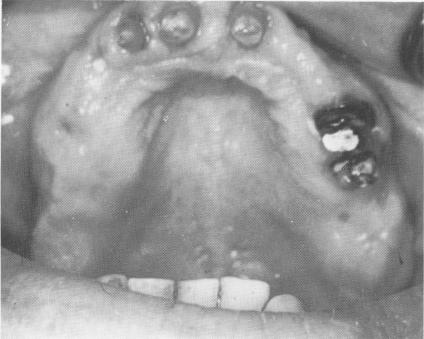

Fig. 11-78. A, The bicuspid implant being placed into the groove. B, Another implant was placed distally in the molar region. C, Another implant was placed in the edentulous area on the opposing side.

1 Maxillary teeth prepared after periodontal therapy

2 Bicuspid blade implant placed into groove in upper jaw